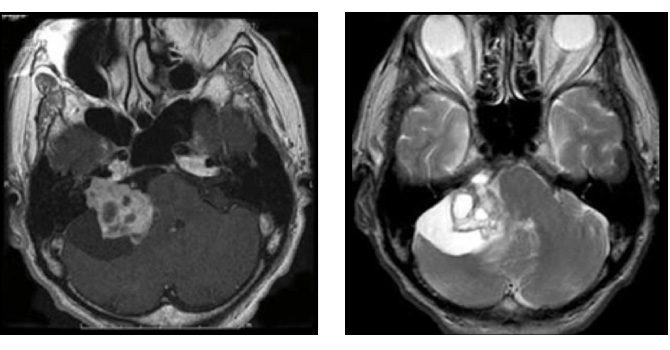

図4:神経繊維腫症2型の症例

42歳女性 両側の聴神経腫瘍をみとめる。NF2の症例。両側とも聴覚は良好であり、大きい方の腫瘍をまず摘出。聴覚は術後やや低下したが温存された。右の小型聴神経腫瘍は拡大傾向なく経過を観察している。

▲ 術前MRI

▲ 術後MRI 左側の腫瘍は被膜を残して摘出されている

▲ 術後左聴覚は25dBまで低下したが、良好な温存。